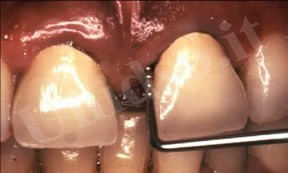

L’ Unità Operativa di Parodontologia e Igiene Orale si compone di 5 sezioni. L’attività’ clinico-assistenziale è svolta da diversi odontoiatri, supportata da igienisti dentali e assistenti alla poltrona, ed è articolata sulla base di appuntamenti programmati. Nell’Unità Operativa di Paradontologia e Igiene Orale del DSMOB si eseguono le seguenti prestazioni odontoiatriche: istruzioni d’igiene orale, ablazione tartaro, full radiografico, terapia dell’alitosi, levigatura radicolare, chirurgia parodontale riparativa, resettiva e rigenerativa e chirurgia plastica dei tessuti molli parodontali.